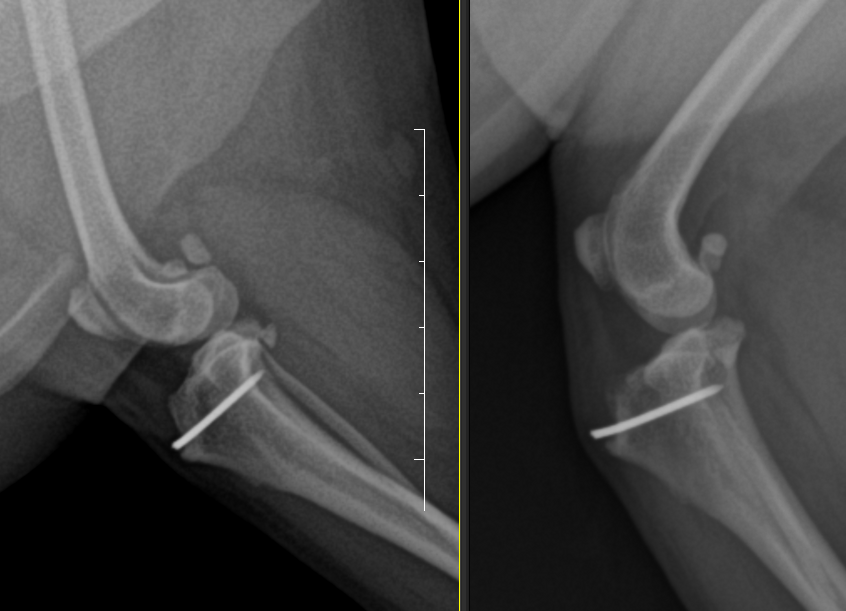

7세 CM 몰티즈, 양측성 슬개골 탈구가 있는 개.

4년 전 심한 슬개골 탈구를 보이며 좌측 후지 파행을 보여 보호자가 좌측 후지만 수술하기로 결정.

이후 우측 파행은 관찰되지 않아 수술을 하지 않음

수술을 한 좌측 다리에서는 경미한 경골 조 면부 enthesophytosis가 관찰된다. 반면 수술하지 않은 우측 다리의 경우는 완전히 다른 예후를 보인다.

관절낭종창이나 관절의 심한 퇴행성 변화 양상은 차치하더라도 경골 조면의 후방의 골 증식양상이 뚜렷하며 이로서 경골의 TPL이 증가한 양상이 관찰된다. 이렇게 되면 십자인대에 가해지는 압력의 크기가 증가하여 십자인대가 파열할 가능성이 높으며 그 증거가 관절낭의 종창이다.